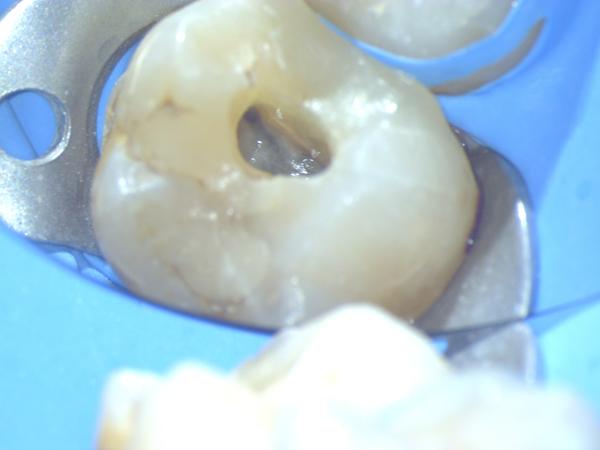

Imágenes: Endodoncia en un molar inferior izquierdo

Reendodoncia